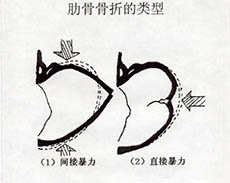

严重颅脑损伤、多发伤、复合伤

疾病介绍:严重颅脑损伤、多发伤、复合伤,多为交通、工矿事故、自然灾害、爆炸、火器伤、坠落、跌倒以及各种锐气、钝器对人体伤害。除正确诊断和及早手术外,加…【详细】